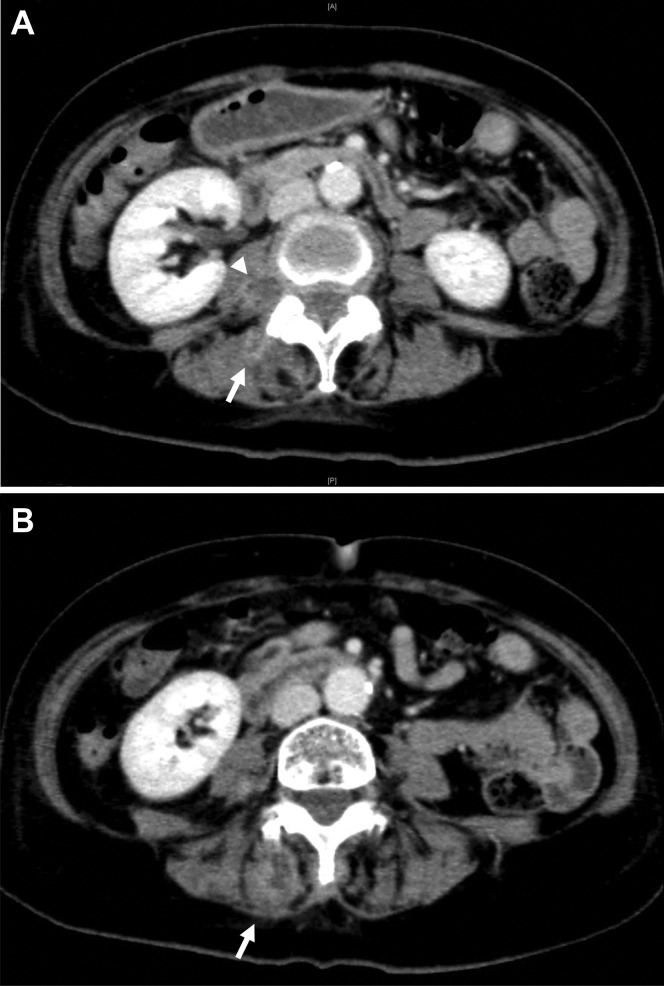

However, like all medical procedures, CAC is not without its challenges. The article provides a detailed account of a rare case where a patient developed symptomatic septicemia following the CAC procedure. This occurrence, while uncommon, underscores the importance of meticulous post-operative care and monitoring.

In the highlighted case, the patient presented with high fever and chills the day after the procedure. Further investigations revealed inflammation and infection of the treated great saphenous vein. The medical team opted for surgical excision of the treated vein to address the issue.